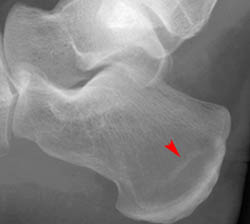

In addition to the anterior and posterior calcaneal fractures shown in the images above, compression and stress fractures of the calcaneus are also common. Look at the two images below showing compression fractures of the calcaneus.

Posterior tangential view

Lateral view